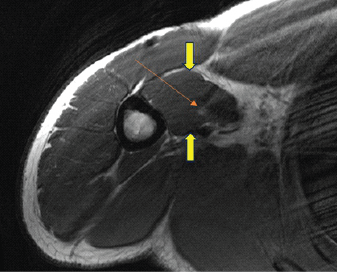

Rare Case of Musculocutaneous Neuropathy in a Professional Baseball Pitcher

Nareka A. Trewick , Olivia B de Araujo , Kerven Cassion , Shelby Burks , Andrew L Sherman , Jean Jose

………………………………p.226-230